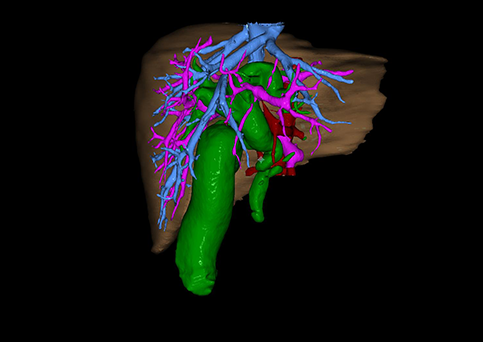

10、三维重建虚拟肝脏、胆道显像技术

三维虚拟肝脏技术是在二维影像学资料如CT等图像的基础上,通过三维重组软件和工具,比如青岛大学附属医院与海信医疗集团联合自主研发的海信计算机辅助手术系统(Hisense Computer Assisted Surgery,Hisense CAS),目前已投入临床并指导实际应用,利用该类系统对二维影像学的数据资料进行三维立体分析,重组形成立体的、有空间结构的、虚拟的肝脏三维图像。这项技术较传统的二维平面成像技术,有着明显的优势,3D虚拟肝脏技术可以构造出一个虚拟的、可视化的肝脏模型。通过对这种模型的观察,可以很容易地分辨出肝脏器官的组织结构、解剖特点,直观研究肝外胆总管的形态差异,明确肝内胆管的形态、走形、是否合并扩张、狭窄及结石,胰胆管合流的形态及共同通道内是否有狭窄、扩张和结石等病变情况,预先规划处理可能合并存在的肝内胆管扩张、狭窄或其他复杂胆道畸形,清晰地显示肝内脉管系统,包括门静脉、肝动脉及肝静脉的走行、分支,并可多角度、全方位观察病变胆道与其周围重要血管尤其是伴行的门静脉之间的解剖关系,大大提高了外科医师在术前对肝脏内部各管道结构及其变异判断的精确性和可靠性,精准地对病变进行判断和评估,还可根据患者自身的病变特点,制定出合理、个体化的手术方案,最大限度地降低术中和术后并发症发生率,并术中导航实时指导手术,提高手术的精准性和成功率。

图10:先天性胆管扩张症囊肿型三维重建虚拟肝脏、胆道显像

a 图为术前二维CT扫描图像,箭头所示为肝内胆管扩张;b 图为CT经多平面重组技术(MPR)图像后处理所得的重建图像,可显示胆总管明显扩张合并肝内胆管扩张;c 图为MRCP显示胆总管呈囊柱状扩张,直径>1 0 cm,伴肝内胆管扩张;d 图示Hisense CAS三维重建清晰显示肝脏、胆道系统及其与门静脉、肝动脉、肝静脉等之间的空间解剖关系;e 图示Hisense CAS可从任意角度以不同脏器组合显示,明确胆道系统与其伴行的门静脉系统的空间解剖关系;f 图示胆道系统立体形态及与肝脏整体的空间关系,箭头处显示肝内胆管狭窄部位发生于左右肝管汇入肝总管处。术前规划需行肝内胆管扩大成形术。

图11:先天性胆管扩张症梭状型三维重建虚拟肝脏、胆道显像

a 图为术前二维CT扫描图像,箭头指示肝内胆管扩张;b 图为CT经多平面重组技术(MPR)所得的重建图像,可粗略地判断病变胆管的位置;c 图示术前Hisense CAS三维重建清晰显示胆管的病理形态及其与肝内三套血管系统的解剖关系;d 图示胆道系统与其伴行的门静脉系统的空间解剖关系;e 图为胆道系统立体形态,箭头处指示迷走胆管,源自肝脏直接汇入胆总管。术前规划先将迷走胆管与肝总管吻合成形,再行肝总管空肠Roux-en-Y吻合术。

图12:先天性胆管扩张症梭状型合并左右肝管分别汇入胆总管囊肿三维重建虚拟肝脏、胆道显像

a 图为术前二维CT图像;b 图为CT经多平面重组技术(MPR)所得的三维重建图像,可粗略地判断病变胆管的位置;c 图为MRCP显示胆总管梭状扩张;d 图为术前Hisense CAS三维重建显示胆管的分布走形及其与肝内三套血管系统的解剖关系;e 图为胆道系统立体形态及与肝脏整体的空间关系,箭头处显示对于左右肝管分别汇入胆总管囊肿中,整个肝总管也明显扩张而成为囊肿的一部分。术前规划为先将囊肿完全切除,左右肝管合并成形后再与空肠吻合。